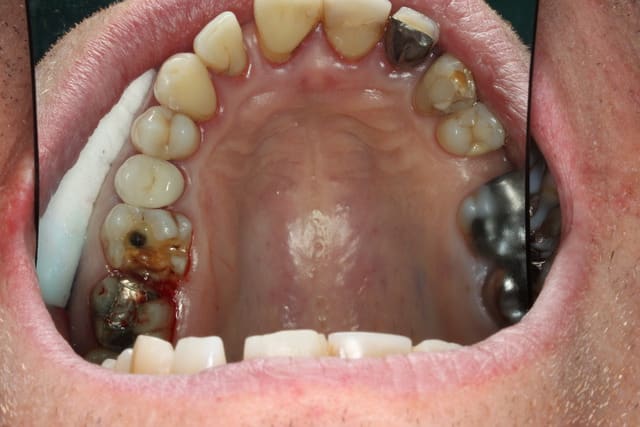

Photo 1. Moi: "Voilà pourquoi il vous faut un onlay."

Photo 3. Le patient: "Ah quand même! Ben on va faire les autres alors!"